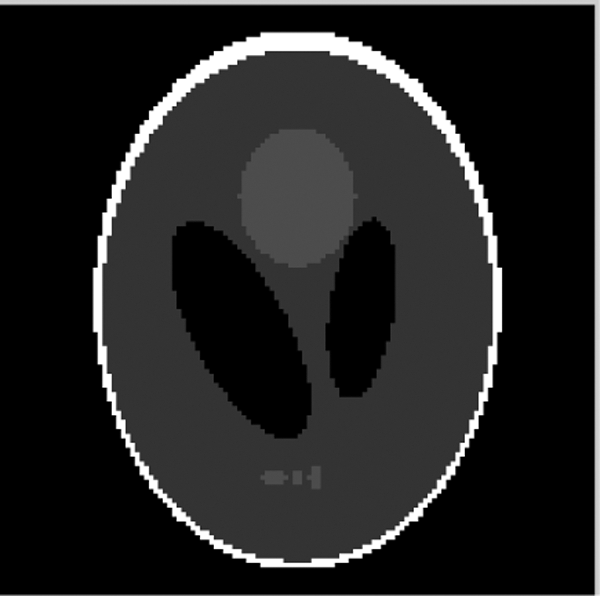

To evaluate the robustness of our reconstruction algorithm, we used a tomographic digital Shepp–Logan phantom. The distribution of projection data is assumed to be generated by 128 angular views (distributed in the range of 180 degrees). Fig. 6 presents the Shepp-Logan phantom image at projection 64.

Figure 6: Shepp-Logan phantom (Projection 64)